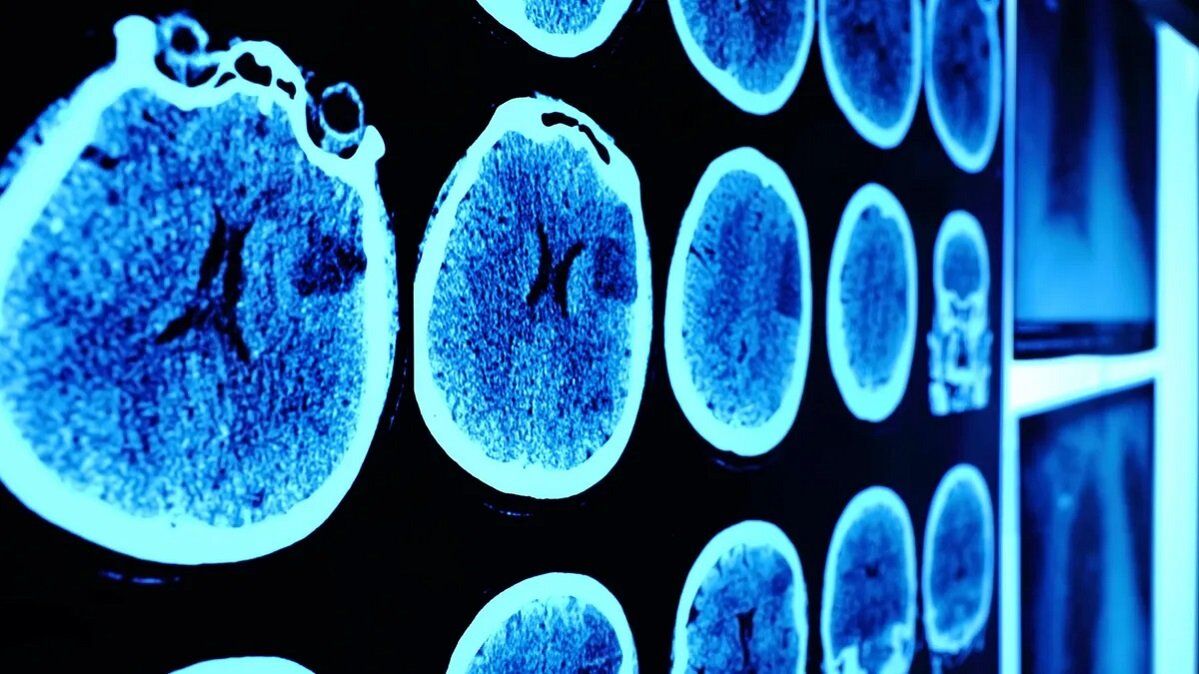

به گزارش سلامت نیوز به نقل از ایسنا، فرآورده دارویی نیکوژن که از سلولهای کشنده طبیعی انسان سالم تهیه میشود، در درمان تومورهای مغزی و بدخیمیهای خونی مورد استفاده قرار میگیرد. این محصول دارویی که توسط یکی از شرکتهای دانشبنیان ایرانی توسعه یافته، موفق به کسب جایزه بریکس شده است و در حال حاضر در فازهای مختلف کارآزمایی بالینی قرار دارد.

در این کارآزماییها، ۱۰ کودک مبتلا به گلیومهای مغزی مقاوم به درمان تحت درمان با سلولهای نیکوژن قرار گرفتهاند. این سلولها که به طور طبیعی قادر به شناسایی و نابودی سلولهای سرطانی هستند، به عنوان یک روش نوین درمانی، در حال بررسی و آزمایش در شرایط بالینی هستند.

نتایج اولیه کارآزماییهای بالینی نشان داده است که استفاده از سلولهای کشنده طبیعی در درمان تومورهای مغزی هایگرید (گرید ۳ و ۴) میتواند تاثیرات مثبت زیادی داشته باشد. برخی از بیماران مبتلا به این تومورها که معمولاً امید به زندگی کمی دارند، پس از درمان با این سلولها تا ۳ تا ۴ سال بدون عود تومور یا با وضعیت پایدار زندگی میکنند.

مدیر فنی این شرکت دانشبنیان اظهار داشت: «نتایج به دست آمده از این کارآزماییها بسیار امیدبخش است. بیماران مبتلا به تومورهای مغزی هایگرید معمولاً بین ۱۲ تا ۱۵ ماه بقا دارند، اما با استفاده از این روش درمانی، برخی بیماران تا ۳ تا ۴ سال از تومور پاک میشوند و یا در وضعیت پایدار قرار میگیرند.»